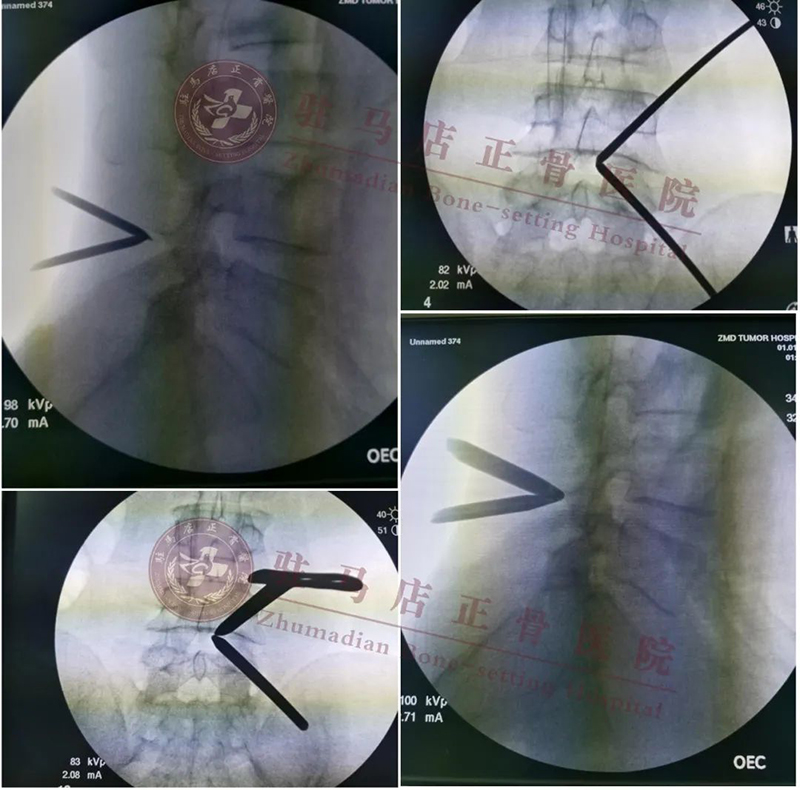

术后影像

➢ 大cage减少融合器下沉及后移

➢ 患者术后早期活动,椎间隙大cage支撑会更稳定

➢ 大cage,可以单边钉棒固定,减少对侧椎弓根及软组织损伤,节约钉棒费用

➢ 大cage可以不用异体骨